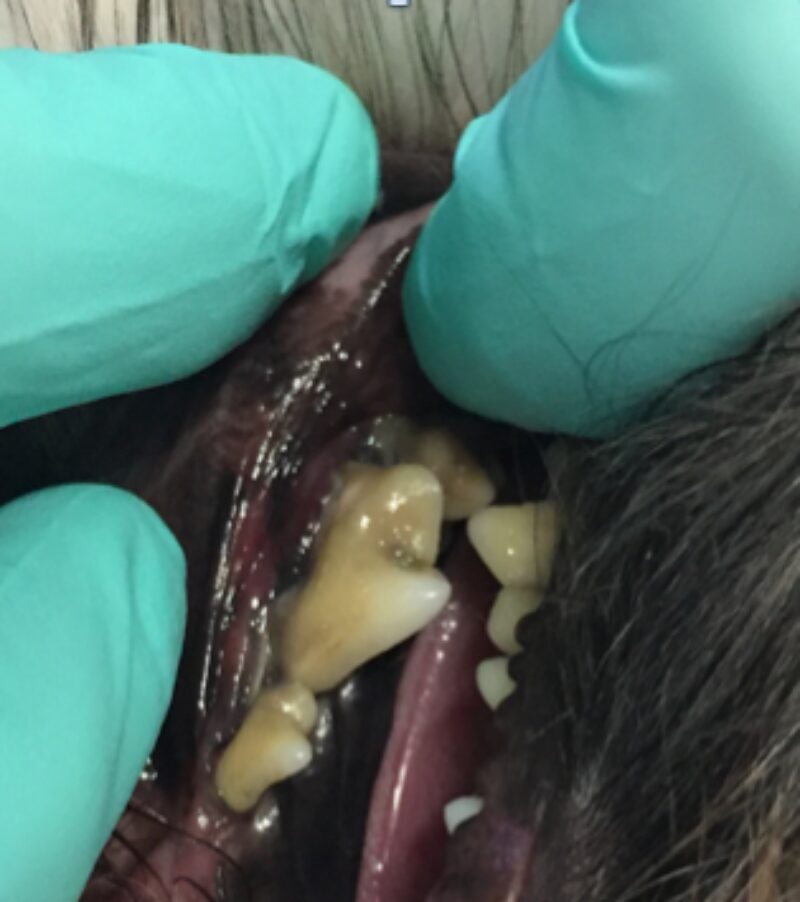

Als ich bei Leila ins Maul schaute, staunte ich schon nicht schlecht. Ich sah die Besitzerin an und fragte: „Wie alt war Leila noch mal?“ Leila war tatsächlich erst drei Jahre alt und doch wusste ich da schon, dass wir wahrscheinlich keinen Zahn retten könnten. Man sieht es wirklich nur, wenn man etwas genauer hinschaut: Leilas Zahnhälse lagen alle frei, und eitrige Beläge kamen aus der Tiefe des Zahnfachs (Abb. 2 - 5).

Solche Veränderungen treten oft bei einer hochgradigen Parodontitis auf. Eine Parodontitis ist die Entzündung des gesamten Zahnhalteapparates (also des Kieferknochens, des Zements, der Paradontalfasern und des Zahnfleischs) und wird durch die Bakterien, welche im Plaque enthalten sind, hervorgerufen. Diese zerstören die Anheftung der Gingiva am Zahn, und die Bakterien können bis zur Wurzel vordringen. Hier rufen sie Entzündungsreaktionen des Kieferknochens und der Gingiva hervor, wodurch beide sich zurückziehen und tiefe Paradontaltaschen entstehen lassen. Doch Leila hatte, wie auf den Bildern schön zu sehen ist, kaum Zahnstein oder Plaque.

Die Ursache hierfür ist eine vorangegangene Zahnreinigung, wobei die oberflächlichen Beläge der Kronen entfernt wurden, jedoch die Entzündung des darunterliegenden Gewebes nicht gesehen wurde.

Es ist sehr wichtig zu verstehen, dass eine Zahnreinigung ohne Aufnahme eines kompletten Zahnstatus inklusive Zahnröntgen nichts weiter ist als eine kosmetische Behandlung, da krankhafte Prozesse übersehen werden (abb. 7-10).